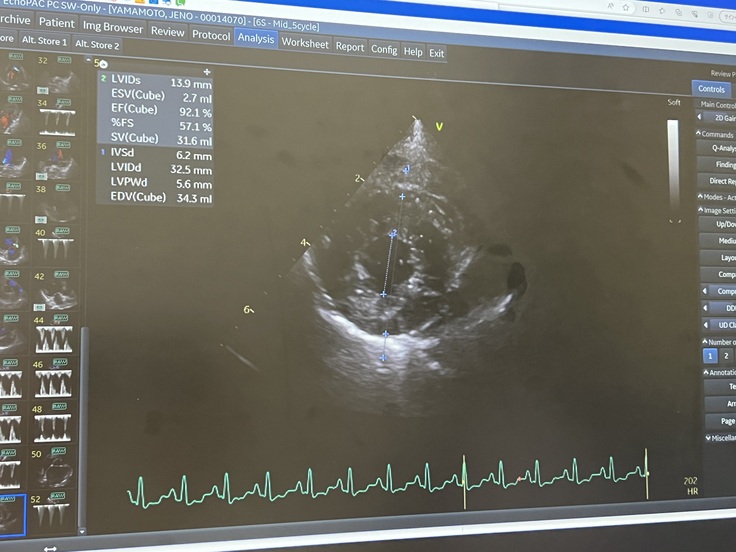

相当悪い状態で、数値も以前より高くなっており、いつ肺水腫になってもおかしくないとの事。